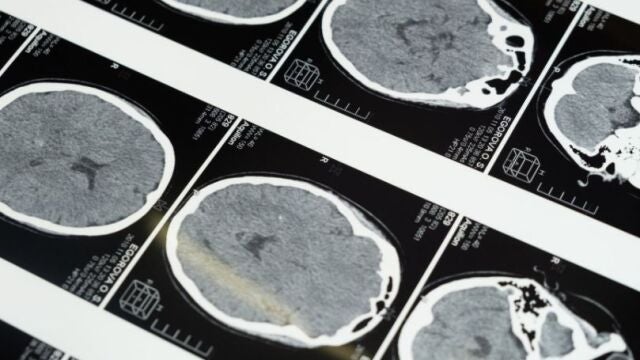

“La actuación frente al ictus ha de ser multidisciplinar y, entre otras disciplinas médicas, el servicio de Logopedia juega un papel fundamental”, aclara Noelia Delgado, responsable de este servicio en el Centro Médico HLA de Toledo. El ictus surge como resultado de un compromiso de suministro de sangre al cerebro.

Atendiendo al tipo de alteración en la circulación hay ictus isquémicos y hemorrágicos. Sus causas son variadas, pudiendo ser una predisposición genética o patologías asociadas como diabetes, estrés o tabaquismo. Sin embargo, también puede ocurrir en personas que no presentan ninguno de estos factores de riesgo.